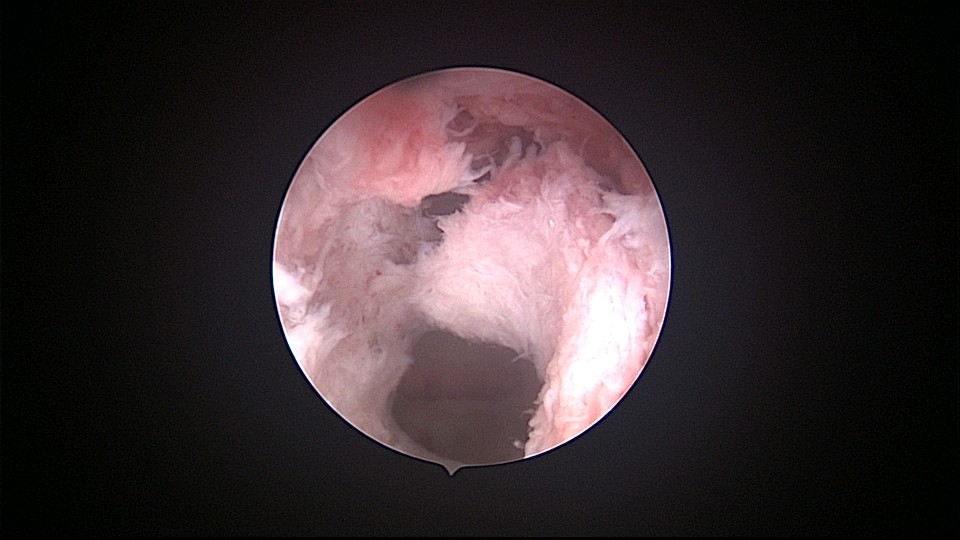

患者54岁,G1P1,顺产1次。安环33年,绝经3年,外院取环失败,子宫穿孔,盆腔积血。子宫后位,宫腔镜见宫颈管组织杂乱,宫颈管上段前壁不规则潜行假道,假道后侧寻找到宫颈内口。扩张宫颈内口,进入宫腔,见O型环位置正常,异物钳取出节育环,宫腔内看不到子宫穿孔。腹腔镜见盆腔积血约400ml,子宫前壁中段偏左见直径0.5cm不规则穿孔,少许渗血,缝合修补子宫穿孔。因左侧卵巢囊肿,患者及家属要求切除双侧附件。